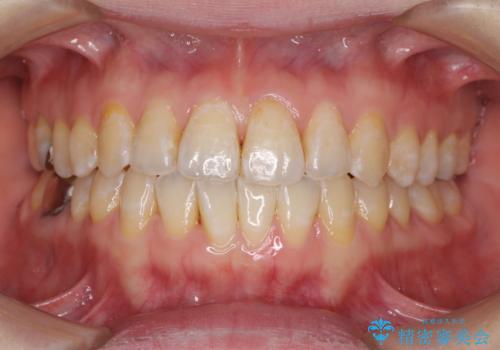

前歯のデコボコを治したい インビザラインによる矯正治療

- 前歯のデコボコを治したいとのことで来院された患者様です。

上下顎ともに歯列全体の後方移動とIPR(歯と歯の間を削る)によってデコボコが解消するように設計し、インビザラインにより治療を行うこととしました。